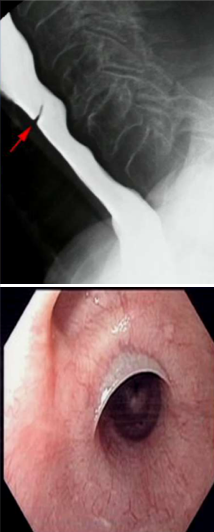

How do you diagnose and treat this patient?

This patient has an esophageal web, which responds extremely well to esophageal dilation.

What type of dysphagia will this patient present with?

Progressive solid food dysphagia. This is a peptic stricture from long standing GERD that has damaged the mucosal lining of the esophagus.